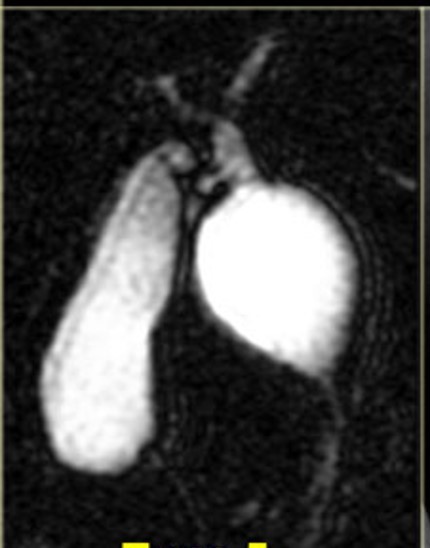

The study is compatible with dilatation of entire extrahepatic bile duct, that’s also known as a true choledochal cyst. Is the type 1 of Todani classification of bile duct cysts.

todani type I

fusiform common bile duct dilation

most common choledochal cyst

tondani type I = fusiform dilation of the CBD